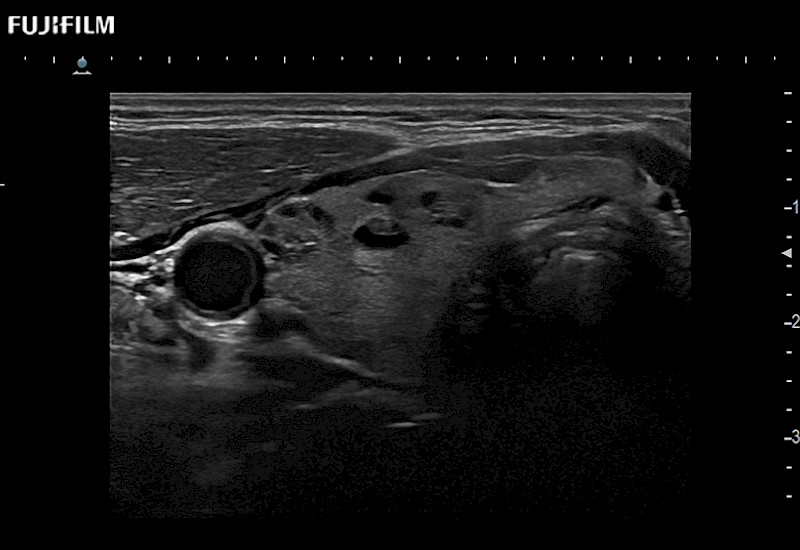

Extraordinary high-resolution digital imaging

Our dedication to Surgical Oncology allows us to offer superior image quality, outstanding system reliability and intuitive use of cutting edge technology.

- Instant feedback on tumor margin delineation

- Valuable information to guide tumor resections

- Instant feedback on tumor margin delineation